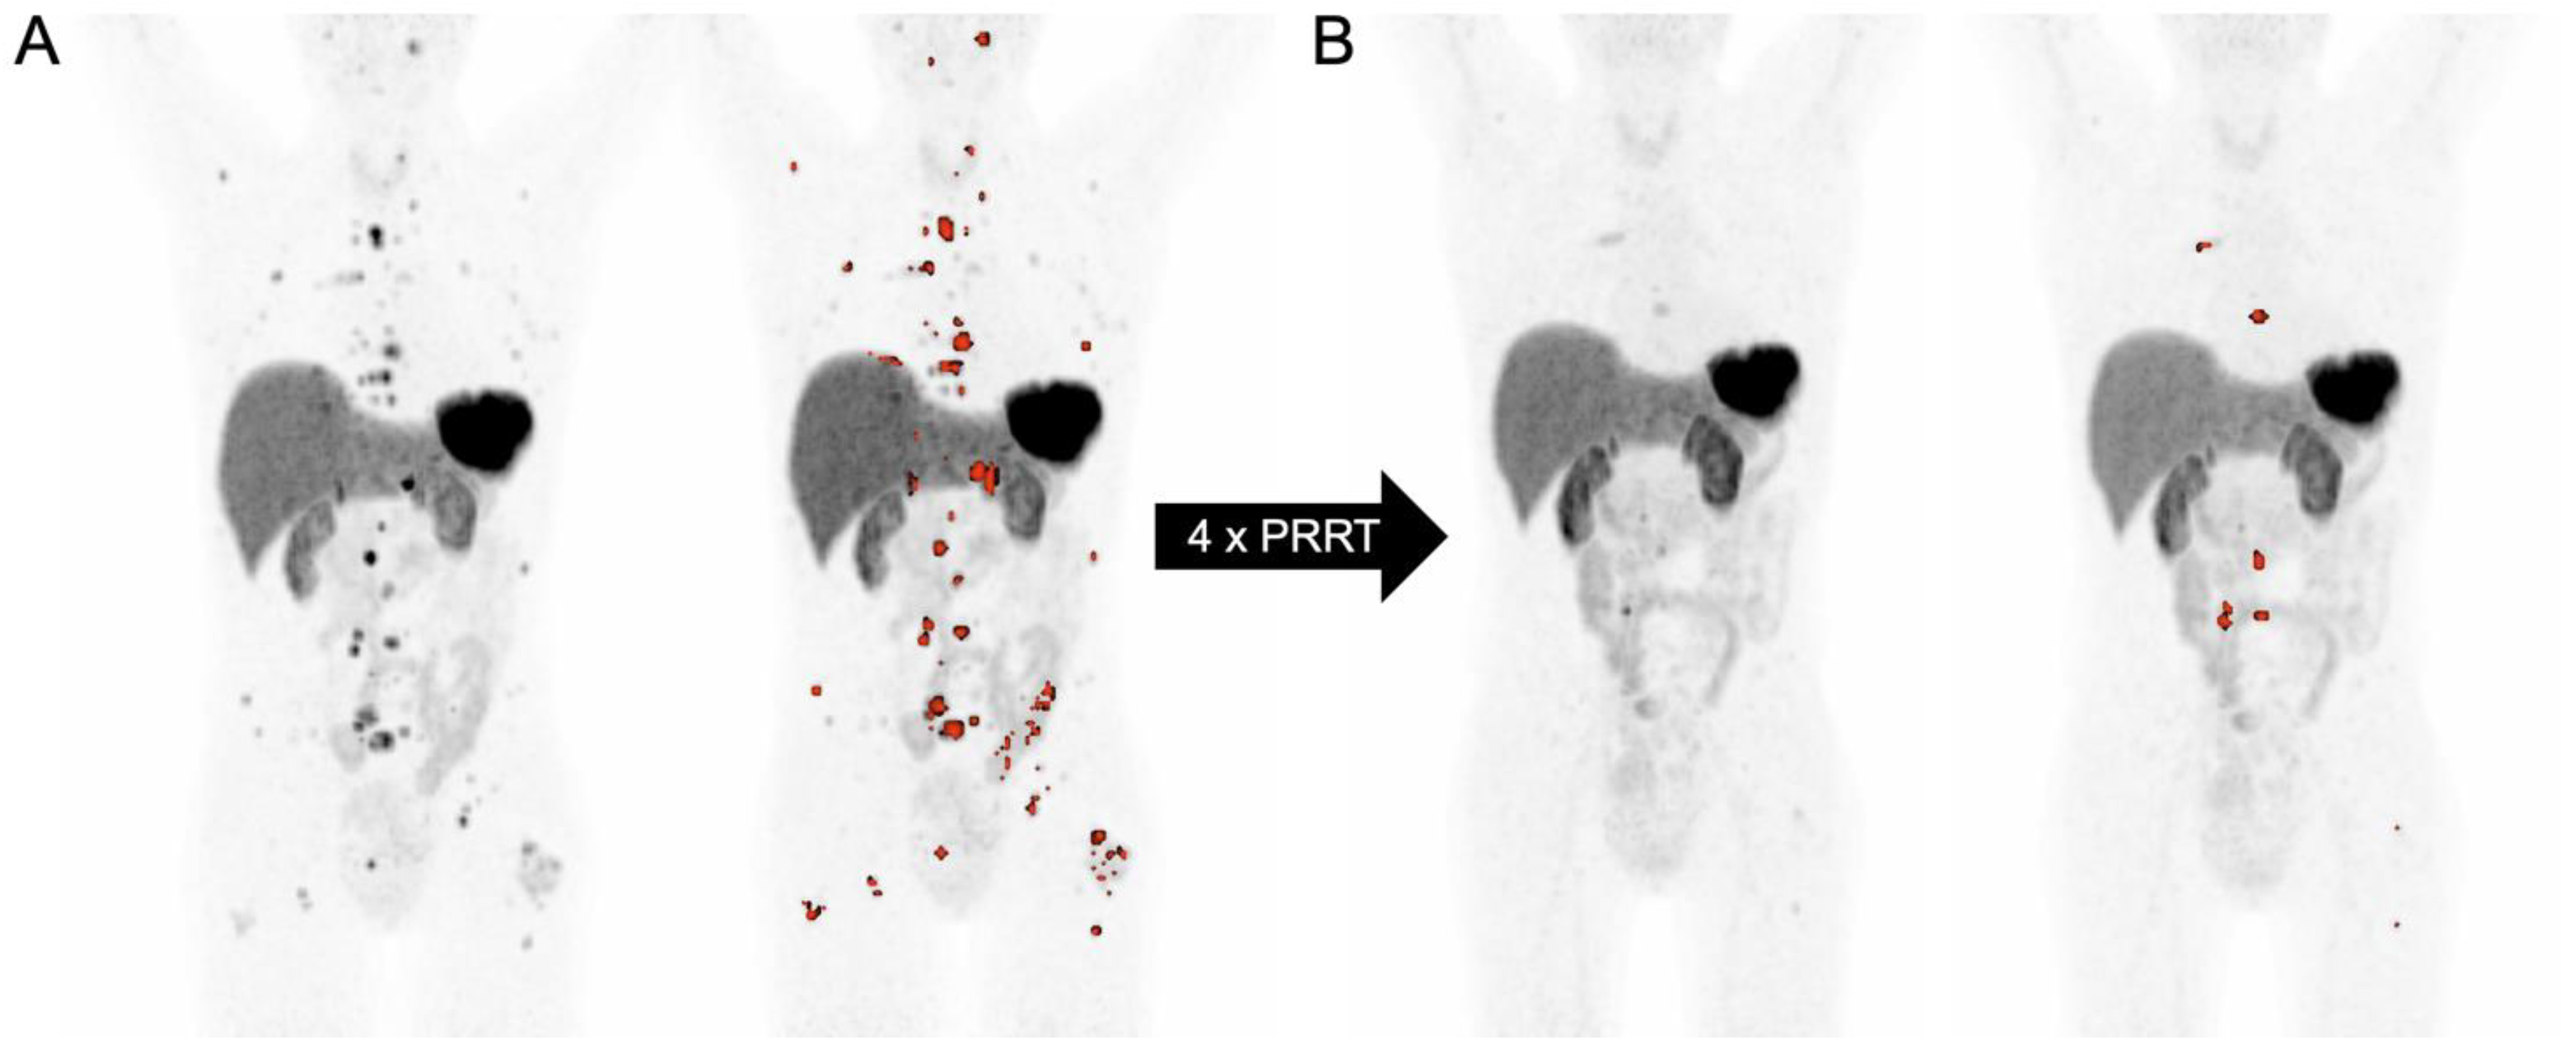

3.7. SSTR-PET-Derived Tumor Volume in the Context of PRRT